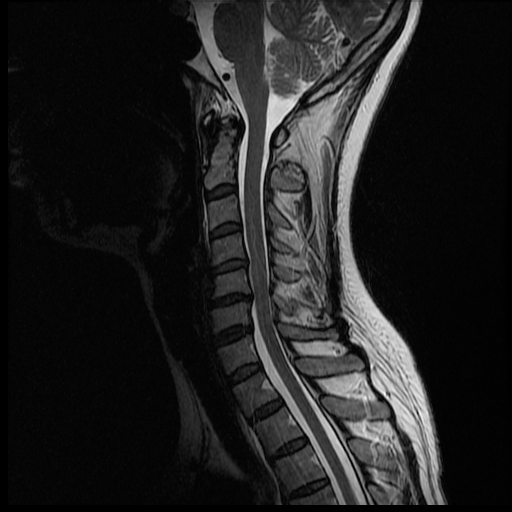

Could not get anybody to read the MRI today. Got pictures home, looked at them. One thing stands out to me. Here is the picture:

Here is the picture this thing doesn't want to work <http://i1131.photobucket.com/albums/m560/chicago-37/MR000005.png>

I cannot tell what the image provided anatomically is or what it means. Is it your neck? This particular view is very hard to decifer for someone who isn't medically trained.

Anyway, if you look at the coronal or sagittal images of the vertebrae, a bony metastasis will often look like a dark erosion within a white vertebrae (T1 imaging). On T1 the vertebrae are usually inform in whiteness and in shape. Metastasis usually appears as dark erosions or as a darkening vertebrae. I'm not sure exactly how they appear on T2 but if you compare the images below you'll see the difference. I'm not sure what C++ means. I've never seen that before.

We will continue to browse and see what pops up...actually shortly after we posted that picture we realized that part of my chin is visualized as well as where the other components of the neck were.....this picture is pretty far from the areas on the bone scan that were bright.

I'm waiting anxiously for Monday morning, but my husband has been pouring over the MRI images most of the night and even this morning. He's not a doctor, but it seems I may have a herniated disc. I hope this is the only thing going on.... The thing is we don't know if this is C6/C7 (where the lesion was seen), or C5/C6. Here are some of the pictures that show that the disc may be bulging/herniated.